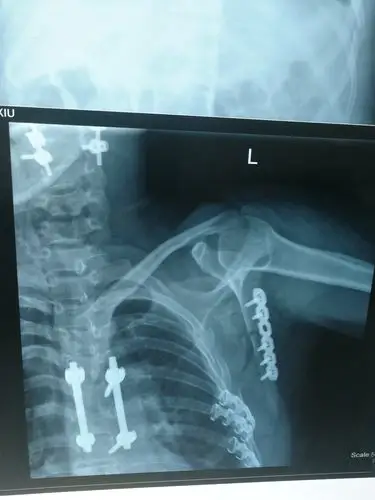

一例肩胛骨骨折的治疗. - 好大夫在线

关节脱位,经手法复位后反复脱位,完善ct发现肩关节前脱位并肩胛盂骨折

肩胛盂骨折,肩袖损伤是否需要手术?

肩胛骨骨折

求助:肩胛骨骨折手术方法

肩盂骨折

上面是肩胛骨骨折.